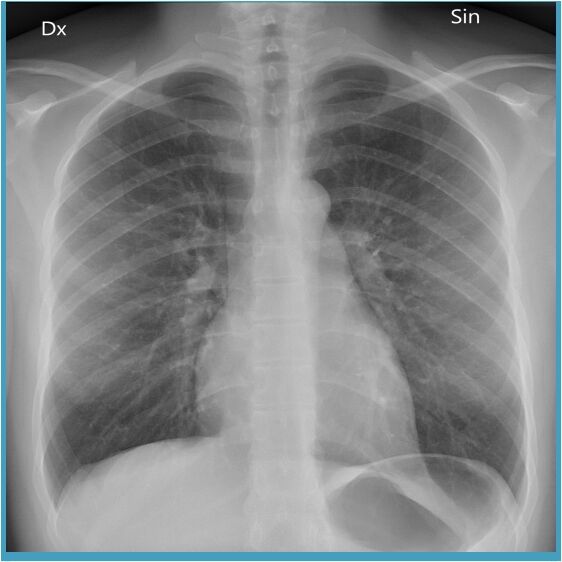

A chest X-ray posteroanterior (PA) view is an imaging test that uses X-rays to look at your chest's structures and organs. It can help find some lung and heart problems and see the insides of the chest, like the food pipe and diaphragm.